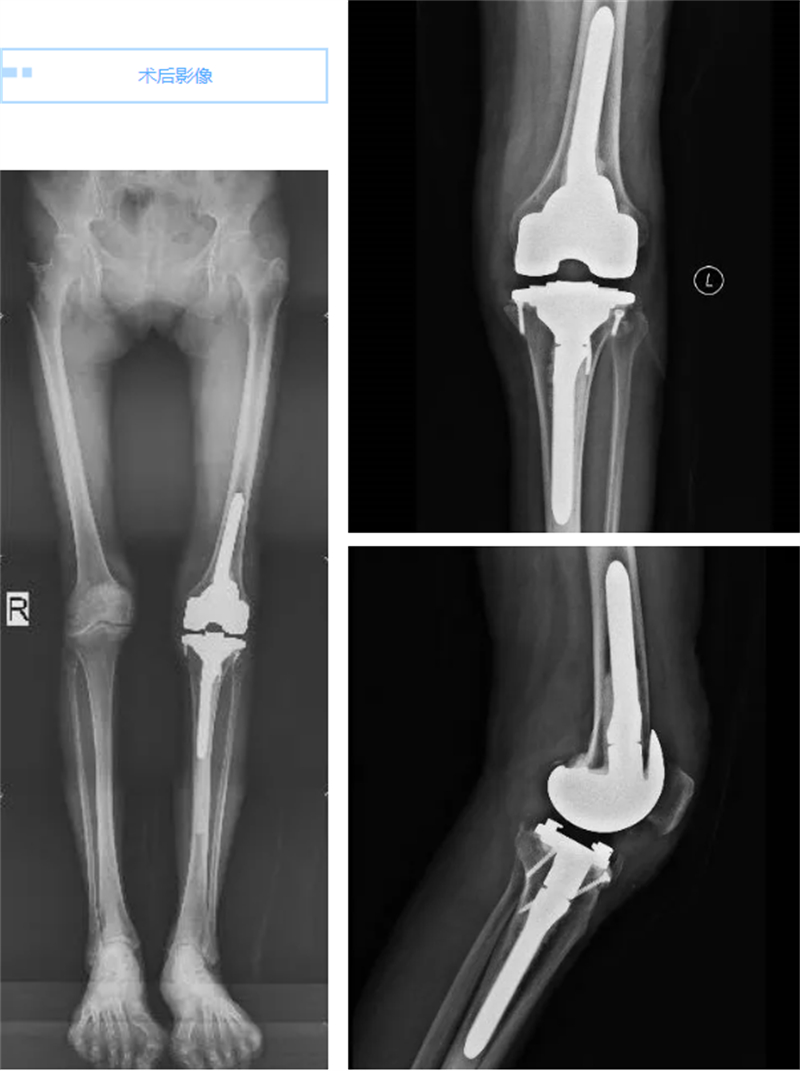

手术过程虽然复杂且技术难度极大,但在关节骨病科专家团队的精心操作下,手术顺利完成。术后当天,当莫女士看到自己的左膝关节重新变直时,她几乎不敢相信自己的眼睛。次日,当她尝试着下地走路时,发现膝关节竟然不再疼痛了,想到出院后能跟姐妹们一起跳广场舞,莫女士笑得合不拢嘴,她仿佛重获了新生,对未来充满了期待。周围的病友们也纷纷向莫女士送上了祝福,夸赞她仿佛重回了“18岁”。

在关节骨病科团队的精心治疗和护理下,莫女士的康复进展顺利,她不仅恢复了健康,更重要的是,她找回了对生活的热爱和信心。相信在不久的将来,就能在广场上看到莫女士翩翩起舞的身影,尽情享受着美好生活。